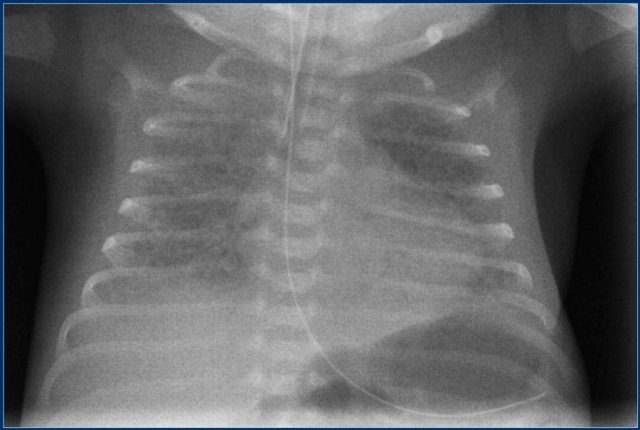

Umbilical artery line (2)

First study the images.

Then continue reading.

The findings are:

1. Umbilical artery line in a good high position.

2. Malposition of umbilical vein line in right portal vein.

3. Skin folds over right basal thorax, which should not be mistaken for a pneumothorax. They typically do not follow anatomical borders.